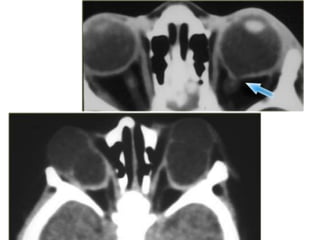

DDx in a child with leukokoria

• Toxocara endophthalmitis

• Persistent hyperplastic vitreous

• Retinopathy of prematurity

• Coat’s disease

• In children

– retinoblastoma until proven otherwise